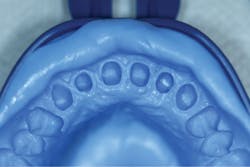

A final impression was made using a base VPS impression material (V-Posil Putty Fast, Voco; figure 11) followed by a light-body VPS impression material wash (V-Posil Light Fast, Voco; figure 12). A provisional crown was made using a cold-cure composite provisional material (Structur 3, Voco; figures 13 and 14) andcemented. The patient was dismissed. Upon return three weeks later, the provisional was removed and the definitive laboratory-fabricated zirconia crown was delivered.

Figure 13: Making of provisional crown

Figure 14: Provisional crown